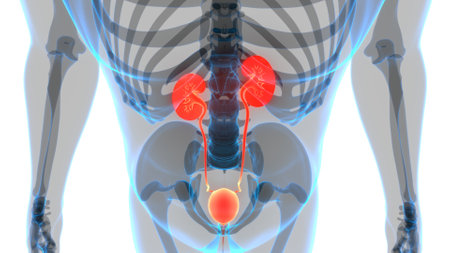

Digital illustration of pelvic girdle in colour background 3D illustration of Human Urinary System Anatomy

3D Medical Illustration Concept of Human Urinary System Kidneys with Bladder Anatomy

Human Urinary System Kidneys with Bladder Anatomy For Medical Concept 3D Illustration